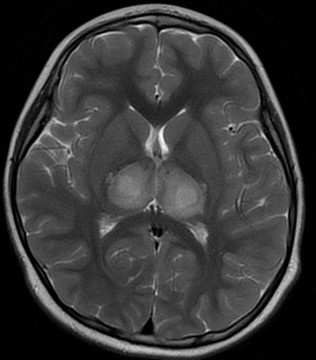

小康入院初时的脑部检查影像图

在急查病原学后,提示其为甲型流感病毒,而小康的头颅MRI检查结果提示其双侧丘脑、双侧小脑半球及小脑蚓部异常信号,经综合研判后考虑是急性坏死性脑病。